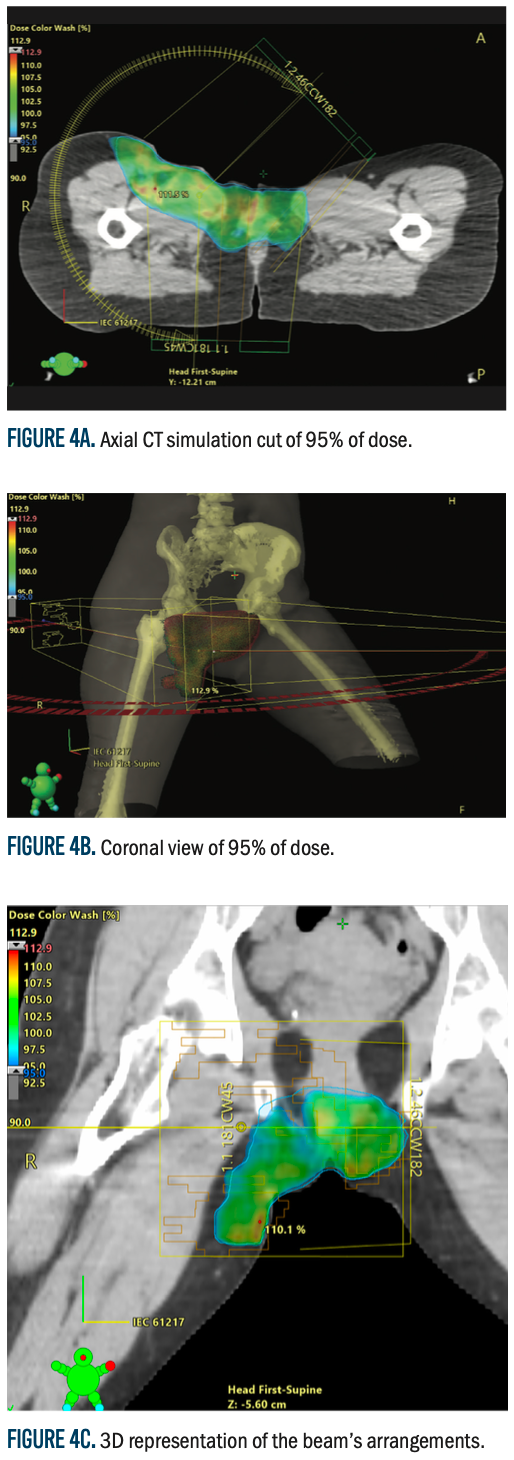

Figure 4a-4c.

CT simulation was performed with the patient in a frog-leg supine position to provide reproducibility and comfort at the time of treatment. A Vac-Lok immobilization device was used to decrease movement and enhance the accuracy of placement. Two CT simulations were carried out, one with a full bladder and another with an empty bladder, to compensate for bladder volume change and organ movement. These images were digitally imported into the Eclipse treatment planning system (software version 15.5, Varian Medical Systems, Palo Alto, CA, for treatment planning purposes. To assist in improving accuracy in target definition, the CT images were fused with diagnostic CT and MRI scans to enhance the accuracy in target delineation.

The clinical target volume encompassed the initial tumor extension, while the planning target volume (PTV) included a 5-mm margin to accommodate setup errors and motion uncertainties. The organs at risk (OARs) considered in treatment planning included the bladder, rectum, femoral heads, and ovaries, ensuring radiation exposure was minimized while maintaining effective tumor control.

A volumetric-modulated arc therapy (VMAT) plan was developed using the TrueBeam linear accelerator (Varian Medical Systems). The plan was optimized using the Photon Optimizer (version 15.5.11, Varian Medical Systems), with dose calculations performed via the analytical anisotropic algorithm (AAA, version 15.5.11) and a 1-mm dose calculation grid. The prescribed dose was 60 Gy in 30 fractions (2 Gy per fraction) to the tumor bed and right inguinal area, delivered at the 90% isodose line with skin bolus application on alternate days for surface dose coverage. The maximum dose to the PTV was 112%, with an average dose of 101%, ensuring optimal tumor control while adhering to OAR constraints.

To confirm patient positioning and treatment delivery accuracy, daily cone beam CT (CBCT) scans were conducted during the course of treatment. This image-guided verification enabled ongoing evaluation of treatment accuracy and position. However, due to severe grade 2 skin toxicity and wound dehiscence, treatment was halted at 46 Gy in 23 fractions instead of the planned 60 Gy in 30 fractions.

Figure 4 (A-E) shows the dosimetric distribution, with an axial CT simulation cut, illustrating the planned radiation coverage and dose distribution within the target volume and adjacent structures. This figure gives a visual impression of dose conformity, with the assurance that radiation delivery was optimized while protecting critical normal tissues.